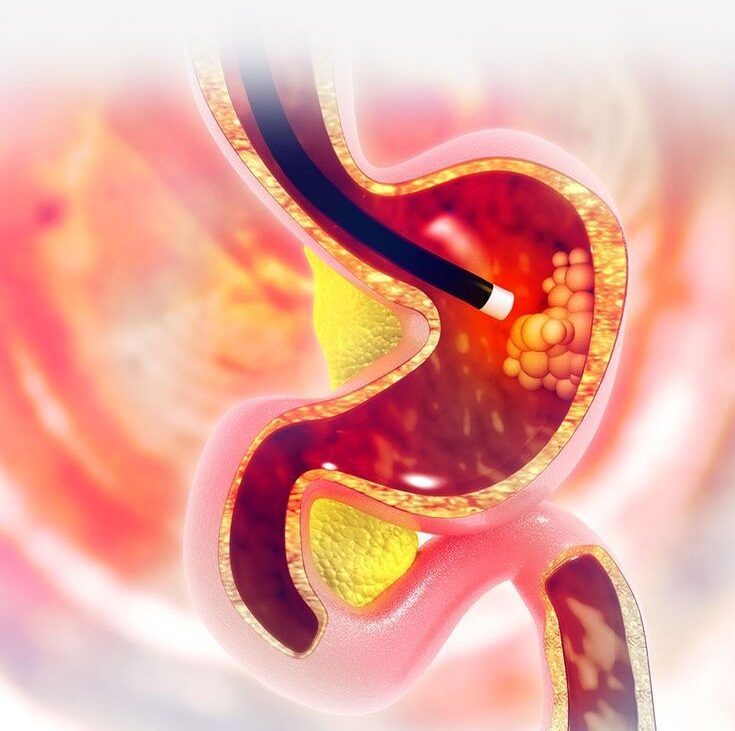

Proctology

Specialized care for anorectal issues with an emphasis on patient comfort and precise treatment.

- Colorectal disorder treatment

Proctology and anorectal care